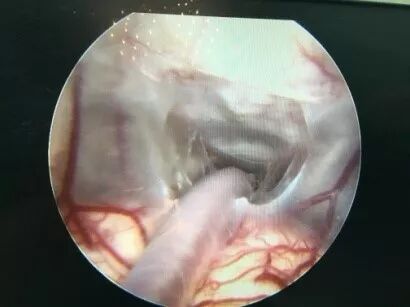

![]()

二次内镜探查可见造瘘口及导水管都是通畅的,考虑患儿存在交通性脑积水,医生使用贝朗蛇牌proGAV2.0分流管 进一步为患儿做了脑室腹腔分流术。